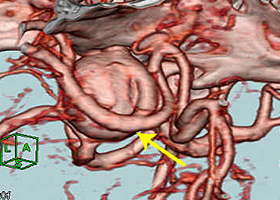

53歳女性、左舌咽神経痛

[画像所見]

-

頭部MRI -

頭部造影三次元CT

左後下小脳動脈が左舌咽神経を圧迫していたために左咽頭部を中心に激しい痛みが生じていました。

体位 -

開頭 -

左後下小脳動脈(黄色矢印)が

左舌咽神経を圧迫 -

左後下小脳動脈を手前に移動 -

減圧完了

[術後画像所見]

術前造影三次元CT -

術後造影三次元CT

左後下小脳動脈(黄色矢印)は術後に本来の位置から移動している。舌咽神経への血管圧迫が解除されたため、術後に患者様は舌咽神経痛が消失した。